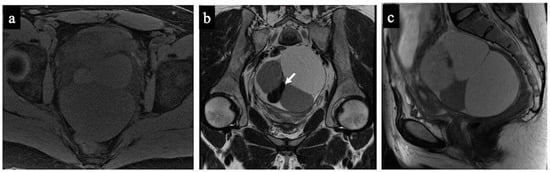

Figure 5. Struma Ovarii. MR images of a 34-year-old woman—16 weeks pregnant—with an indeterminate adnexal mass accidentally discovered at first trimester US. The axial T1 with fat saturation (a) and coronal (b) and sagittal T2-WI (c) images show a multilocular cystic mass with different signal intensities within the loculi. Some loculi have a very low signal intensity on the T2-WI (white arrow in image (b)) corresponding to colloid. No solid tissue is seen within the lesion; thus, it was correctly considered as benign/NCMS 2 according to both readers (true negative).

Figure 6. Low-grade ovarian serous cancer. MR images of a 33-year-old woman—7 weeks pregnant—with bilateral indeterminate adnexal lesions discovered at the 6-week US. The axial T2-WI (a), DWI (b) and ADC-map (c) show bilateral adnexal masses with papillary projections and mural nodules (solid tissue) within the lesions (arrows). Solid tissue has an intermediate signal on T2-WIs and corresponding true diffusion restriction. Free pelvic fluid is seen in the pouch of Douglas. No carcinosis was present, so the lesions were correctly classified as malignant/score 4 by both the readers (true positive). Note the gestational sac in the uterine cavity (arrowhead).